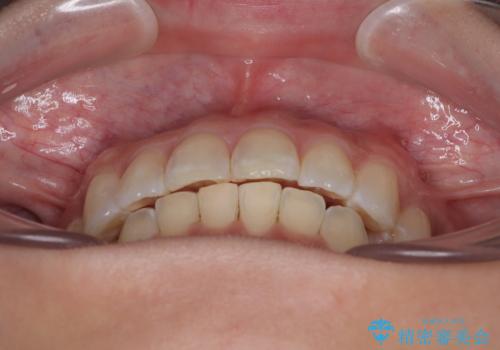

なかなか舌の突出癖が改善できず、上下前歯が非接触となる期間が長く続きました。

アンカースクリューの活用と、舌のトレーニングを何度も指導し、出っ歯になることなく無事に治療を終えることができました。